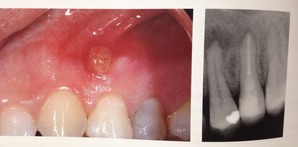

先日に書いたように完全に細菌を取り除くことはできません。

ので、外科的な治療が必要な歯もあるんです。

こんなに大きな穴でも、治ります。

少し根っ子を削るので、短くはなりますが。